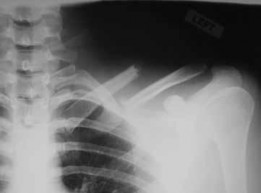

Figure 23Figure 23 is the radiograph of a 22-year-old woman who was involved in a motor vehicle collision. She reports isolated pain in her left shoulder. She is hemodynamically stable, respiring comfortably, and neurovascularly intact. Based on these findings, which of the following statements regarding treatment is most appropriate?